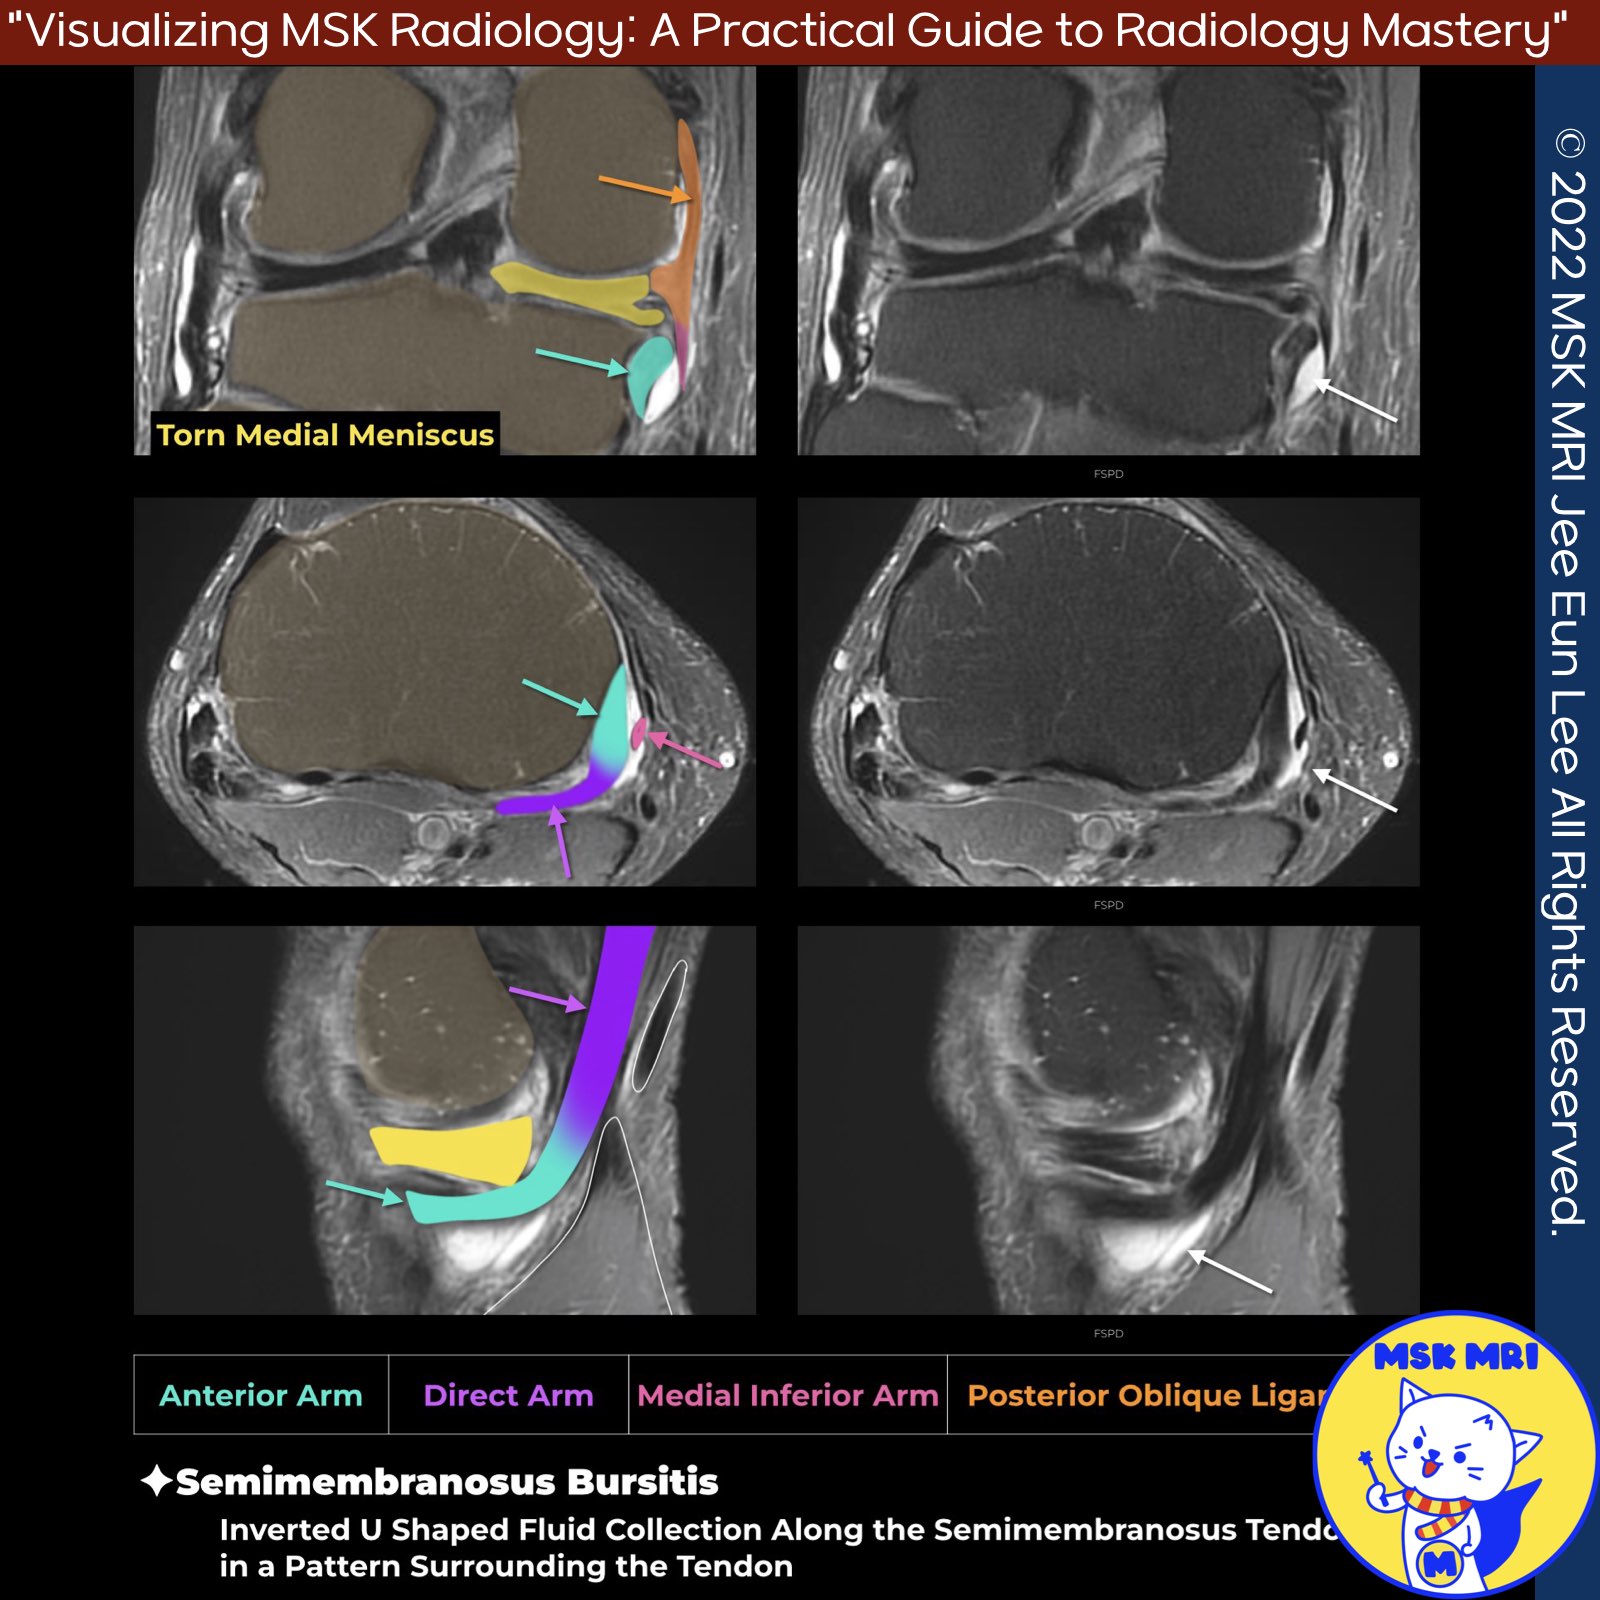

✅Semimembranosus Bursitis Overview

- The semimembranosus bursa, a horseshoe-shaped synovial bursa, is located around the semimembranosus tendon near the posteromedial tibial rim. When inflamed, it forms a synovial-lined space that wraps the tendon, visible as a characteristic reverse 'J' shape on imaging.

✅Direct Arm Anatomy

- The Direct Arm of the semimembranosus tendon attaches directly to the posteromedial aspect of the tibia, just distal to the joint line.

✅Anterior Arm Details

- The anterior arm inserts into the medial proximal tibia, above the insertion of the superficial MCL, and passes beneath the posterior oblique ligament. It has an almost horizontal course and is visible on coronal images as a round, hypointense structure adjacent to the medial tibia, under the MCL.

🔹Posterior Oblique Ligament Connection

- The posterior oblique ligament attaches to the sheath of the semimembranosus tendon, blends with the posterior margin of the superficial MCL, and runs superficially to the anterior arm of the semimembranosus tendon.

✅ Inferior Arm Divisions

- The inferior arm of the semimembranosus tendon is split into medial and lateral divisions.

- The medial division attaches to the medial tibia and extends anteriorly toward the posterior margin of the medial collateral ligament.

- The lateral division passes over the popliteal fascia and the popliteus muscle, further emphasizing its structural significance.